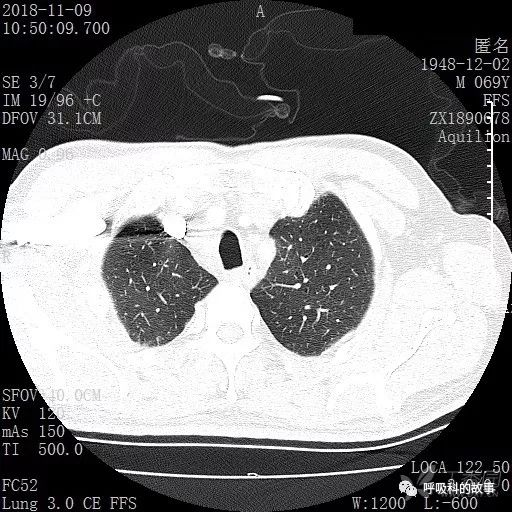

胸部增强CT示右肺门占位伴远端阻塞性肺炎,纵膈、右肺门、右侧颈根部、右侧腋下及肝门部肿大淋巴结。两侧胸腔少量积液。

肺窗CT